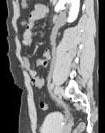

问题 男,29岁,反复发作血尿1年余,CT如图所示,下列说法正确的是 ( )

选项 A、左输尿管结石 B、膀胱结石 C、左侧输尿管扩张 D、左侧输尿管末端,膀胱入口处可见高密度影 E、左侧肾盂扩张积水

答案 ACDE